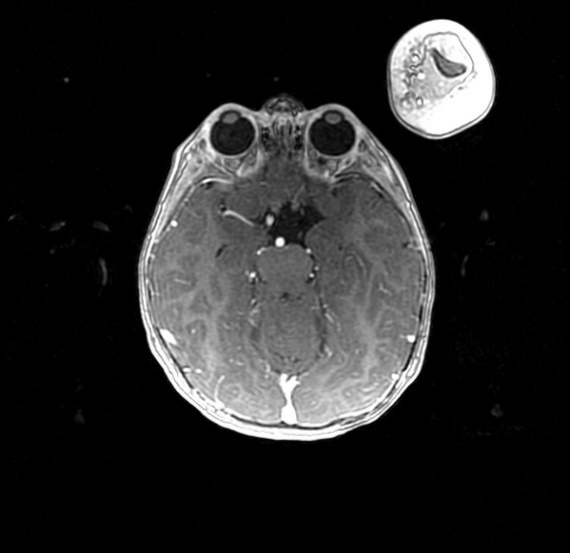

MRI findings showed the lack of the normal flow void of the left internal carotid canal and the first part of the left middle cerebral artery (Figures 1 and 2). The pituitary gland is flat. No evident anterior or posterior pituitary gland tissue or pituitary stalk is observed. The pituitary gland's strong posterior signal is not detected in situ or

ectopic. The left medial cerebral artery originates within the posterior circulation, and the left internal carotid artery cannot be seen. No intra, supra, retro or parasellar masses. Normal MRI appearance of the optic chiasm and corpus callosum. Otherwise, normal MR appearance of the brain parenchyma with no definite focal lesions. Diagnosis of congenital panhypopituitarism associated with agenesis of ICA was made.

a)

b)

c)

d)

Figure 2. a-c) show coronal MRI brain images, and d) is a view in which the left midcranial artery is coming from the posterior circulation and the left internal carotid artery is not visible (agenesis).